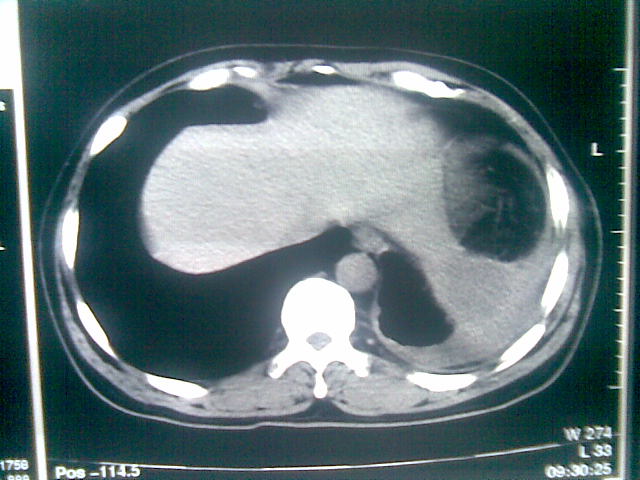

标题: CT23981:男,38岁阑尾炎术后透视胸腔积夜!做CT如下!积液包 [打印本页]

标题: CT23981:男,38岁阑尾炎术后透视胸腔积夜!做CT如下!积液包

可能与阑尾术后关系不太大,1.胸膜增厚粘连见少量气体。包裹脓气胸?左侧网膜囊脓肿?

.胸膜增厚粘连见少量气体。包裹脓气胸

左侧胸膜增厚、粘连+包裹液气胸。